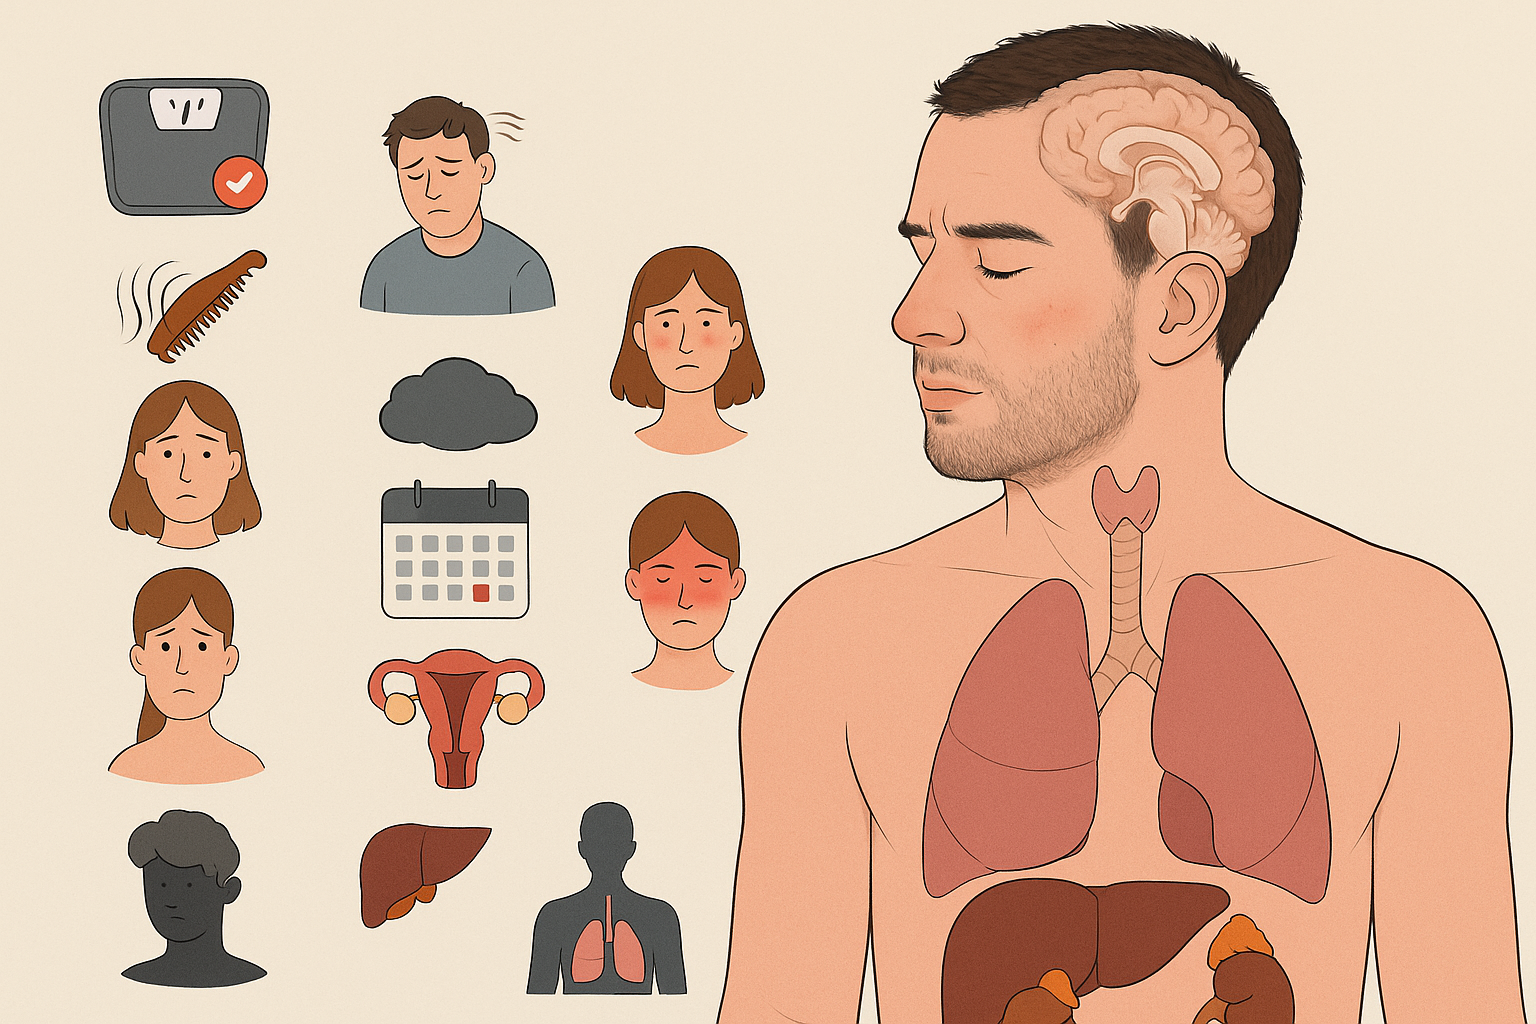

علائم و علل عدم تعادل هورمونی

عدم تعادل هورمونی میتواند باعث بروز علائمی مانند خستگی، تغییرات خلقی، اختلالات خواب، افزایش یا کاهش وزن و مشکلات پوستی شود. آشنایی با علل و نشانههای این وضعیت، نقش مهمی در پیشگیری و درمان بهموقع آن دارد.

نشانههای عدم تعادل هورمونی چیست؟

از آنجا که بدن انسان بیش از ۵۰ نوع هورمون تولید میکند و هرکدام در فرآیندهای حیاتی نقش دارند، طبیعی است که علائم این اختلال میتواند بسیار متنوع باشد. بسته به اینکه کدام هورمون دچار نوسان شده است، نشانهها نیز متفاوت خواهند بود.